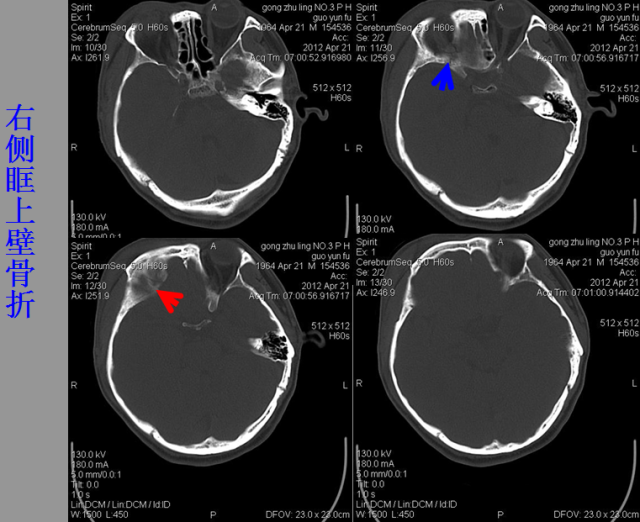

急性颅脑损伤篇

03